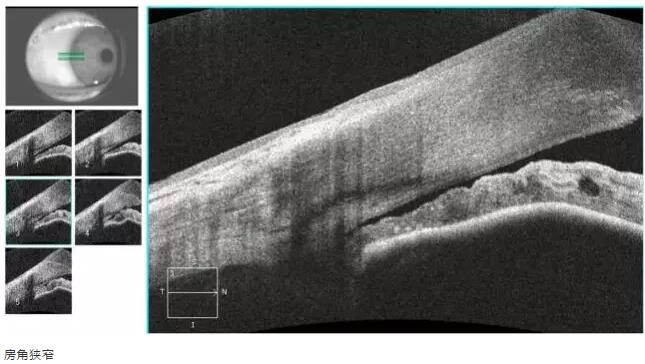

青光眼篇

1:OCT 前节断层扫描可识别出巩膜突、Schwalbe 线 、Schlemm 管 等结构,且辨识度很高,巩膜突(78.9%)、Schwalbe线(93.3%),若对图像进行放大查看, 更佳。